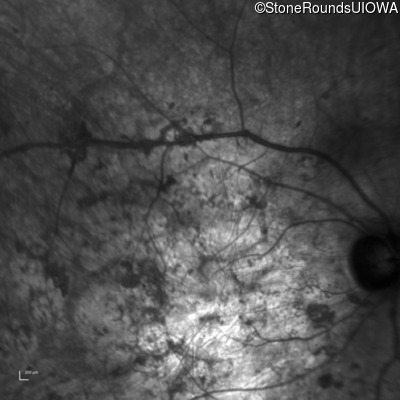

Infrared Fundus Photograph - Right - Hand Motion sc

Exemplar

Infrared Fundus Photograph - Left - Hand Motion sc